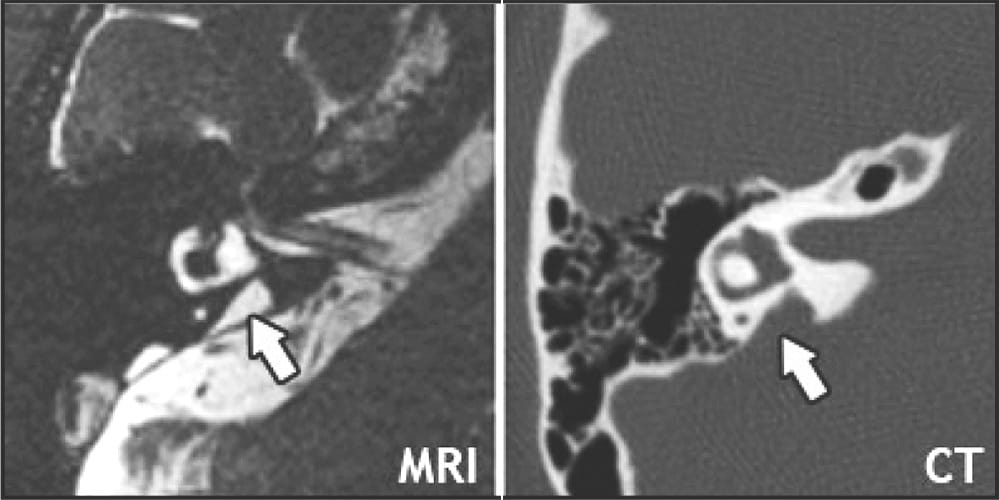

Once sensorineural hearing loss has been confirmed, imaging scans such as magnetic resonance imaging (MRI) and computed tomography (CT) may be recommended to evaluate the inner ear structure. Although most imaging results are normal, when there is an anatomic abnormality, EVA is the most common.